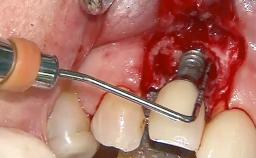

Despite anti-infective surgical treatment, some patients may experience recurrent infection and progressive bone loss requiring additional treatment. Removal of Implant Due to Recurrent Infection describes a conservative approach using an implant retrieval tool without the need for excessive bone removal or use of a trephine.

A 70-year-old female patient was referred by her general dentist to the periodontist for assessment and management of an infection associated with implant 36. The general dentist had noted suppuration on probing during examination.